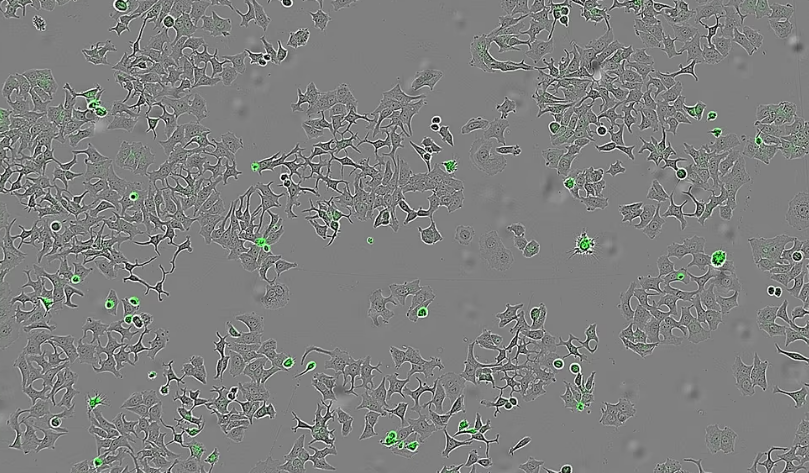

To confirm that HapA was responsible for the effect, scientists conducted experiments using mutant strains of V. cholerae that lacked the protein, as well as bacteria genetically modified to produce only HapA. In every case, tumour cells only died when HapA was present, confirming its decisive role in reducing cancer cell viability.

The researchers further tested the protein’s impact by exposing cancer cell lines from breast, colon, and pancreatic tumours to liquids containing all the proteins secreted by V. cholerae. “We wanted to see if human cells of different tumour types were still alive and could multiply after being in contact with these bacterial substances — particularly HapA,” Hurtado explained.